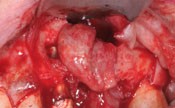

Caso clinico di cisti Apico-Radicolare

Immagine iniziale

Incisione del lembo

Scollamento del lembo

Esteriorizzazione della cisti

Svuotamento del contenuto cistico

Pinzettamento della cisti

Enucleazione della cisti

Cavità ossa residua

Cavità riempita con biomateriale

Posizionamento di una membrana

Sutura del lembo

Immagine della cisti rimossa